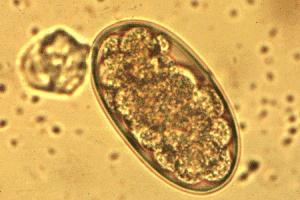

4- Anguillule : Strongyloides westeri

Photo Laboratoire Mérial

Morphologie : Petits nématodes de 2-9 x 0,5 mm, seules les femelles sont parasites. Œufs larvés, à coque mince, à bords arrondis et côtés parallèles, mesurant 45-50 x 30 µm.

Localisation : Intestin grêle

Epidémiologie : Infestation par ingestion de larves infestantes, par pénétration percutanée des larves ou par le lait de la jument. Pathologie des poulains, souvent jeunes. Migration somatique passant par les poumons avant de revenir à l'intestin. Elimination d'œufs larvés qui évoluent sur sols humides en larves infestantes après avoir donné une génération d'adultes libres (mâles et femelles).

Etude clinique : Agent d'une entérite diarrhéique du poulain, grave avec hyperthermie.